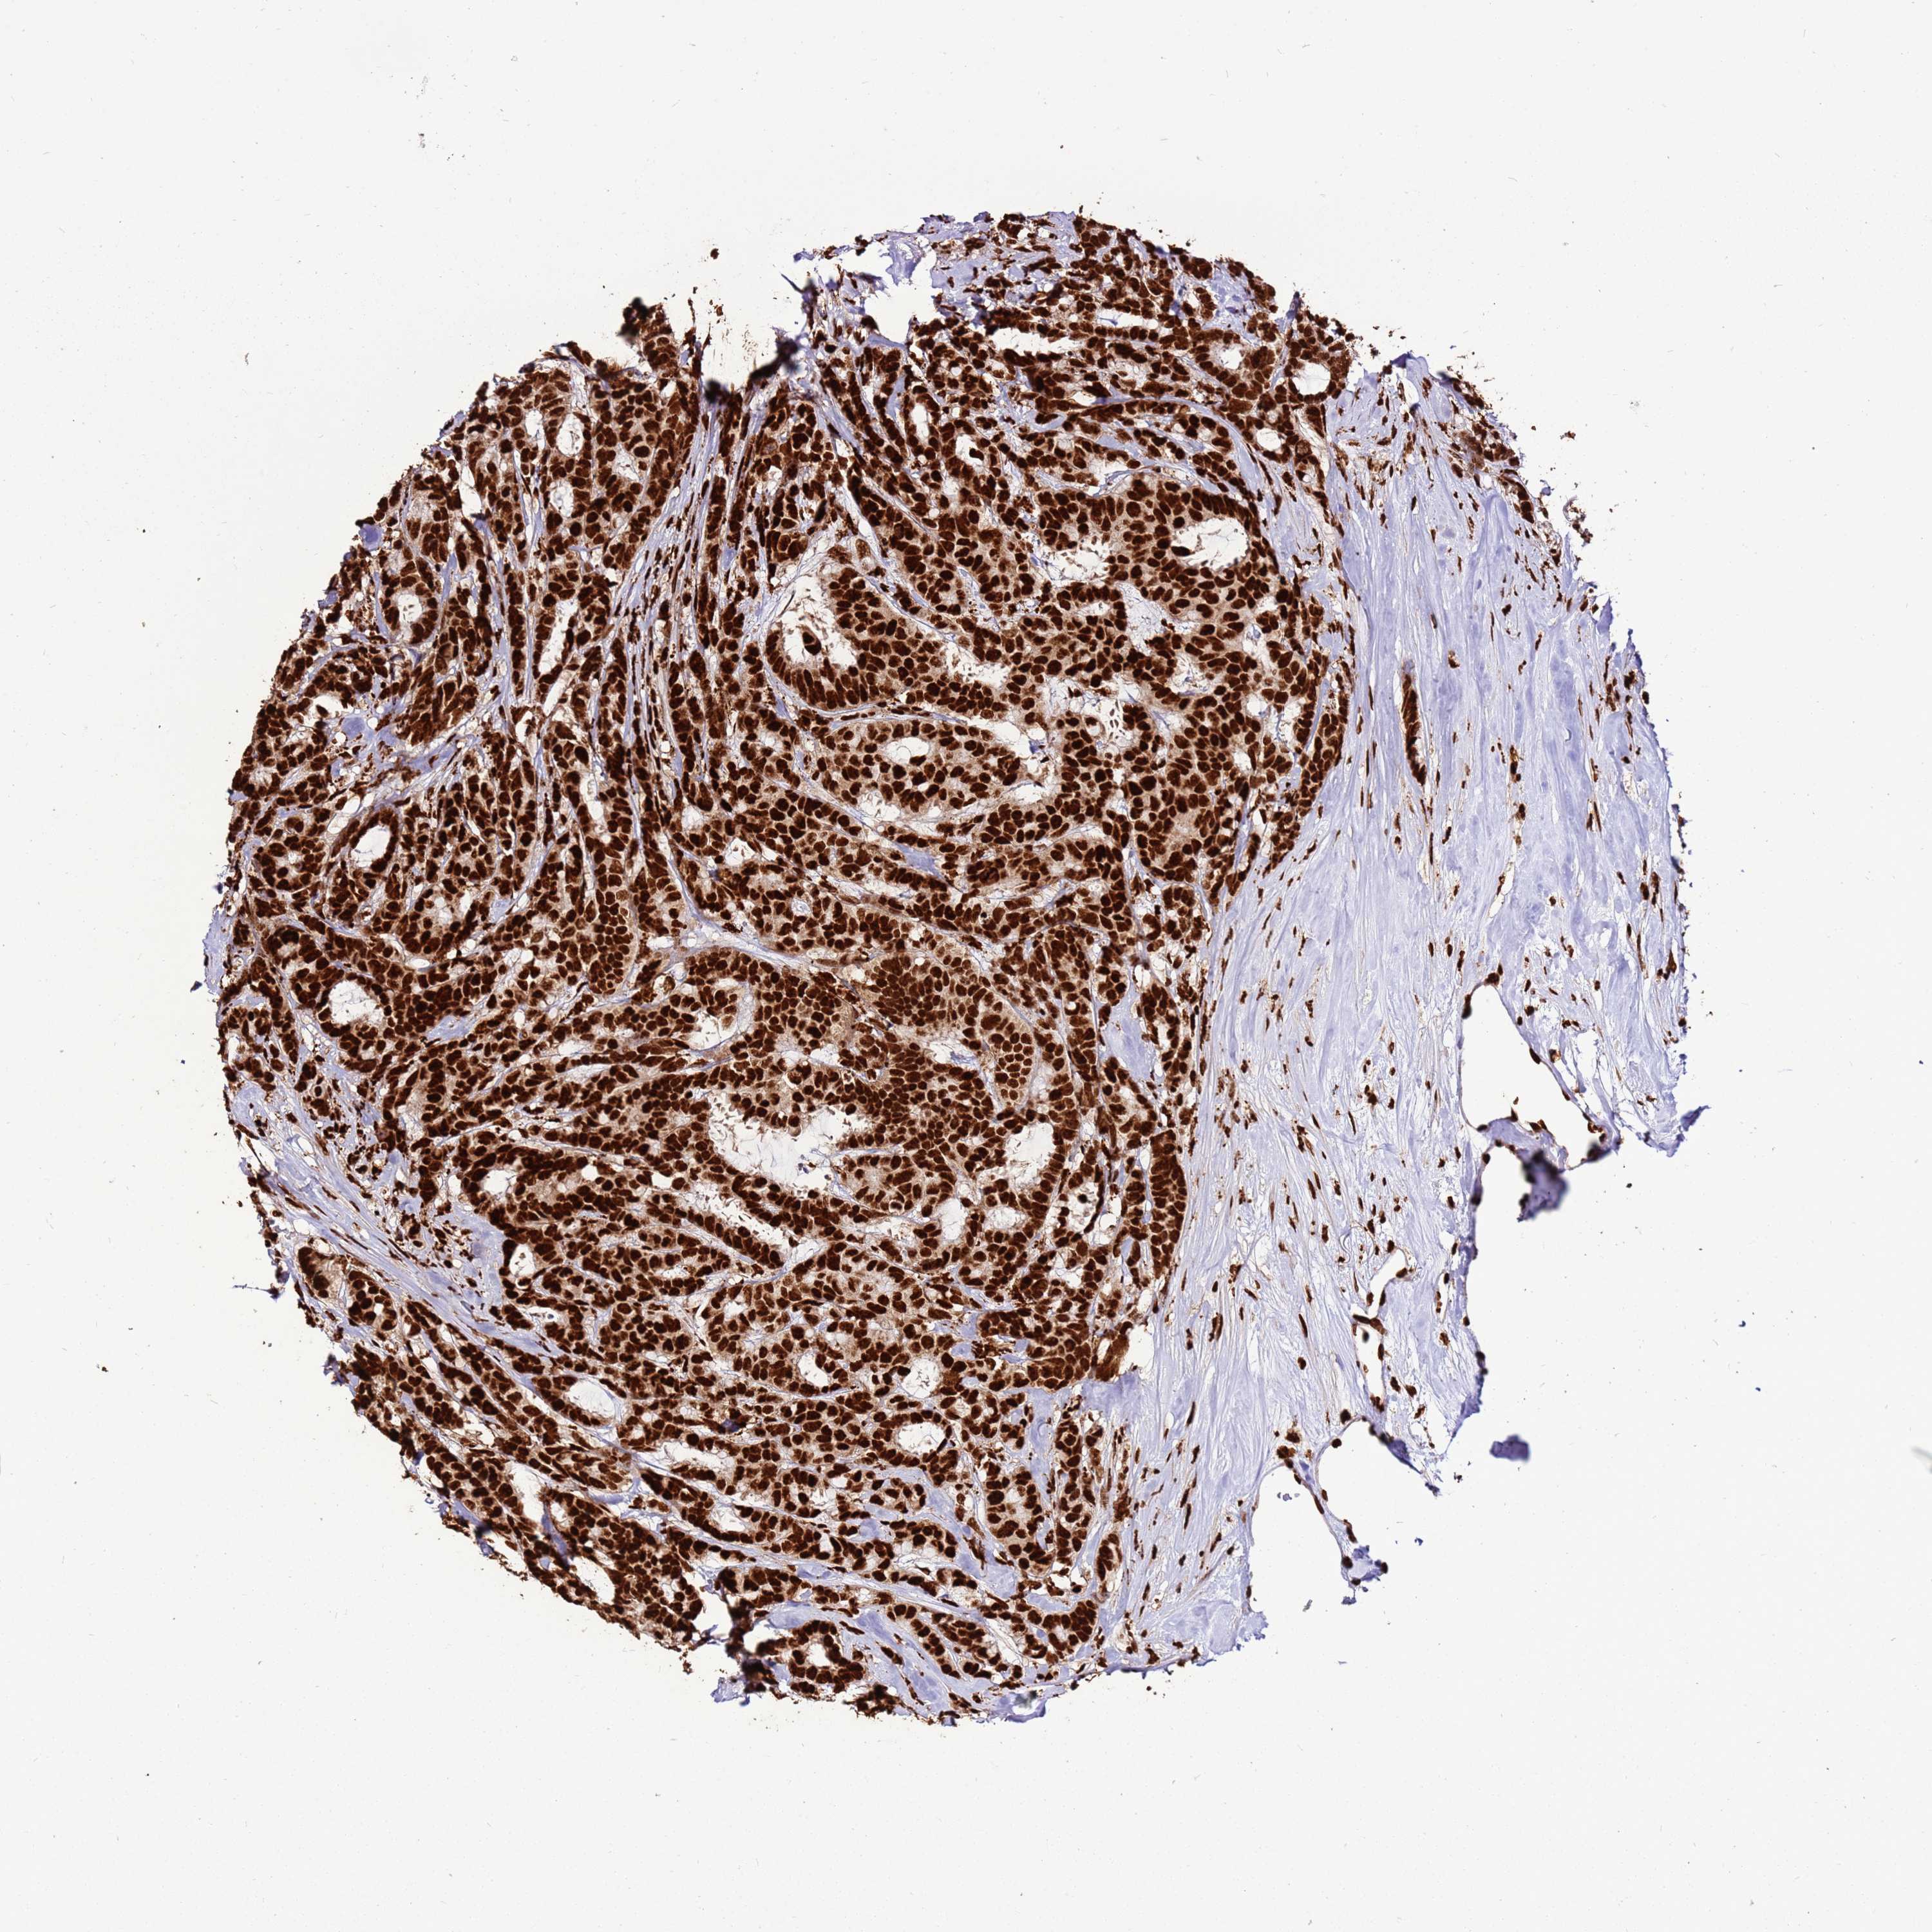

CANCER BREAST CANCER Show tissue menu

BRCA TCGA BRCA VALIDATION PROTEIN EXPRESSION